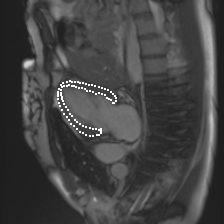

Accurate segmentation and motion estimation of myocardium have always been important in clinic field, which essentially contribute to the downstream diagnosis. However, existing methods cannot always guarantee the shape integrity for myocardium segmentation. In addition, motion estimation requires point correspondence on the myocardium region across different frames. In this paper, we propose a novel end-to-end deep statistic shape model to focus on myocardium segmentation with both shape integrity and boundary correspondence preserving. Specifically, myocardium shapes are represented by a fixed number of points, whose variations are extracted by Principal Component Analysis (PCA). Deep neural network is used to predict the transformation parameters (both affine and deformation), which are then used to warp the mean point cloud to the image domain. Furthermore, a differentiable rendering layer is introduced to incorporate mask supervision into the framework to learn more accurate point clouds. In this way, the proposed method is able to consistently produce anatomically reasonable segmentation mask without post processing. Additionally, the predicted point cloud guarantees boundary correspondence for sequential images, which contributes to the downstream tasks, such as the motion estimation of myocardium. We conduct several experiments to demonstrate the effectiveness of the proposed method on several benchmark datasets.